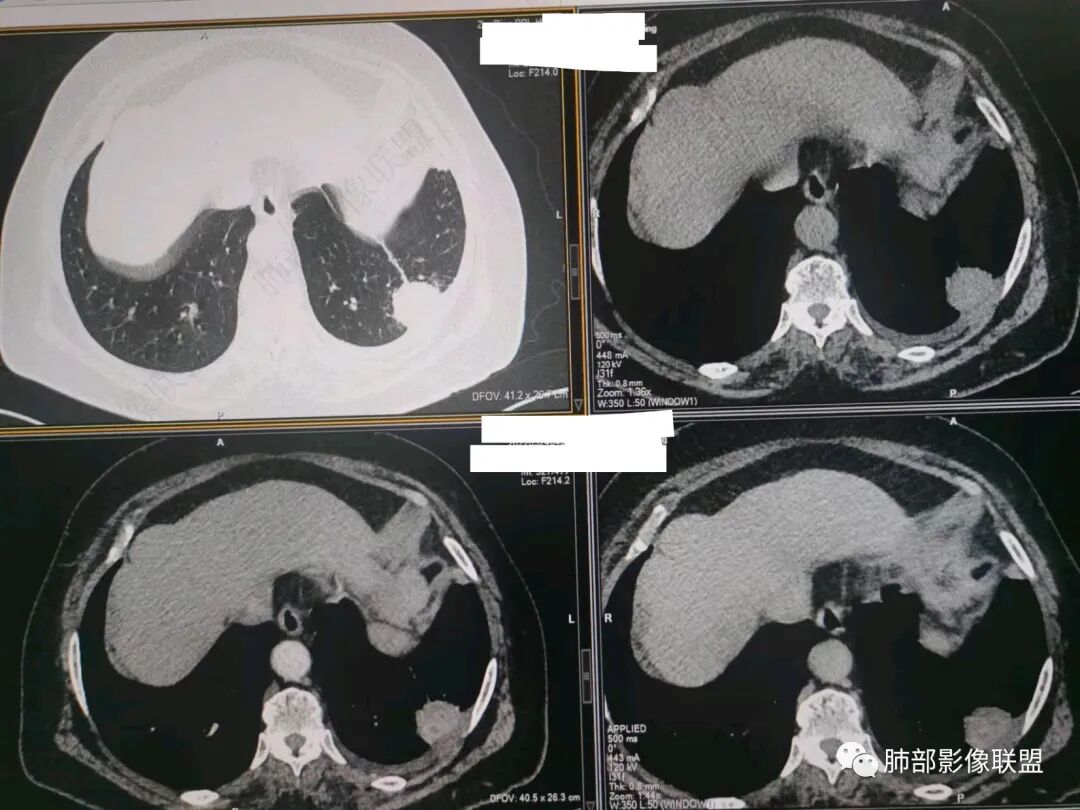

南边:今天的病例肺内部分基本都是炎性特点,问题就在于胸膜。

糊墙:肺内病灶不侵犯壁层胸膜或以外,与壁层胸膜相对而言分界清楚。

栽赃:病灶侵入壁层胸膜及胸膜外脂肪间隙、胸壁其他结构等,相对在病灶中央区域,与胸膜分界不清。

南边:看肺内病灶与胸膜分界清,增强后强化不一致,需要综合分析。

这是糊墙。

这就栽赃。都突到外面去了。

看看这个,骨头都侵袭了。

南边:一般这类侵袭,是中央地带毛刷状延伸到胸膜内。

我只是邓较瘦:南大这个我感觉局部似乎是栽赃呢 箭头那里是啥?

南边:栽赃是这样过去的,中间不会脂肪间隙清晰。

胸壁的组织,除非你怀疑胸壁转移结节。

转移淋巴结。

局部侵犯。有差异。

我只是邓较瘦:这个是侵犯出去不是淋巴结吧?

南边:不是,你看看强化与淋巴结不一致。

我只是邓较瘦:强化与肿瘤差不多。

南边:是。